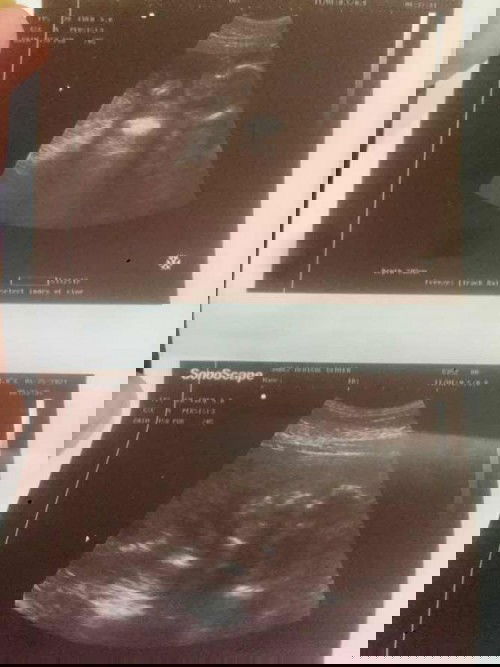

Hello po! May maalam po kaya bumasa neto? Okay ba ang amniotic fluid ni baby sa loob? Thank you.๐โค๏ธ